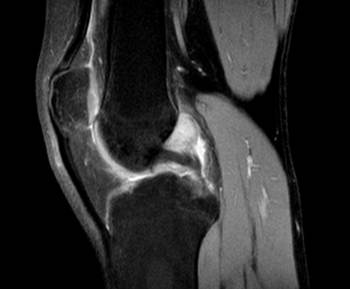

Se realiza tratamiento quirúrgico inicialmente mediante artroscopia diagnóstica, identificando lesión tumoral a través de portales artroscópicos habituales asociados a los portales postero-externo y postero-interno (ver imagen 2). Posteriormente se realiza un abordaje con capsulotomía posterior de rodilla izquierda, para llevar a cabo la exéresis de la tumoración (ver imagen 3).

Imagen 3: Exéresis de tumor de células gigantes focal mediante abordaje y capsulotomía posterior de rodilla izquierda.